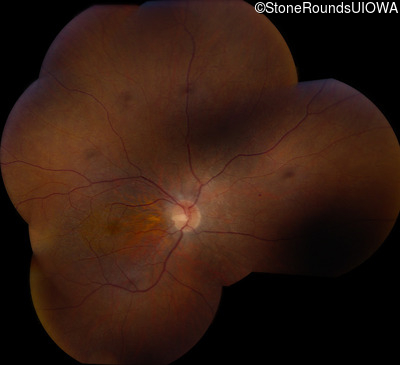

Fundus Montage - Right - 20/50 +1

Exemplar